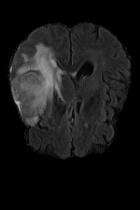

Current unsupervised anomaly localization approaches rely on generative models to learn the distribution of normal images, which is later used to identify potential anomalous regions derived from errors on the reconstructed images. However, a main limitation of nearly all prior literature is the need of employing anomalous images to set a class-specific threshold to locate the anomalies. This limits their usability in realistic scenarios, where only normal data is typically accessible. Despite this major drawback, only a handful of works have addressed this limitation, by integrating supervision on attention maps during training. In this work, we propose a novel formulation that does not require accessing images with abnormalities to define the threshold. Furthermore, and in contrast to very recent work, the proposed constraint is formulated in a more principled manner, leveraging well-known knowledge in constrained optimization. In particular, the equality constraint on the attention maps in prior work is replaced by an inequality constraint, which allows more flexibility. In addition, to address the limitations of penalty-based functions we employ an extension of the popular log-barrier methods to handle the constraint. Comprehensive experiments on the popular BRATS'19 dataset demonstrate that the proposed approach substantially outperforms relevant literature, establishing new state-of-the-art results for unsupervised lesion segmentation.